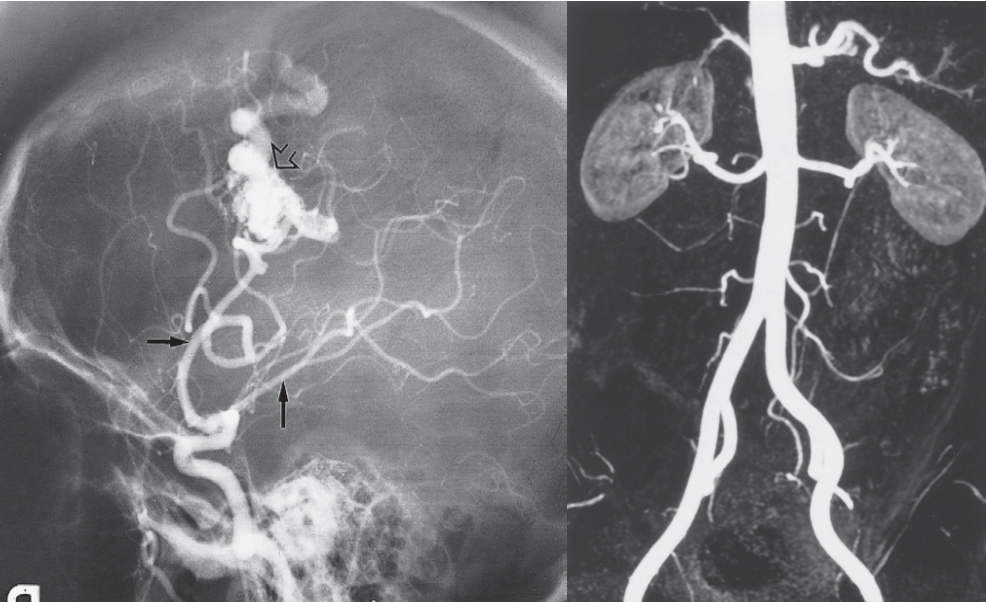

Digital subtraction Angriography & MRA; MRI Modality

contrast: Iodine base